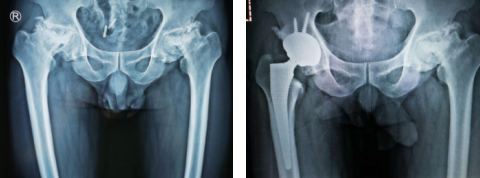

杨沛霖医生接诊,经过片子的检查,发现该患者双侧股骨头无菌性坏死,股骨头骨质碎裂、塌陷,骨片移位。患者髋关节已经受到严重破坏,无法正常行走、上下楼,影响了正常生活,右侧尤为严重,保守治疗已经无法奏效,邱东新副主任医师手术团队经过商量,决定给患者进行右侧人工全髋关节置换手术。

次日,手术进行。邱东新医师手术团队以右髋关节外侧改良Gibson入路,切除已经坏死的股骨头,进行髋臼磨造,置入髋臼假体,拧入螺钉固定;置入股骨假体,测试髋关节活动无脱位,透视见全髋关节位置合适,仅一个半小时,手术顺利完成。